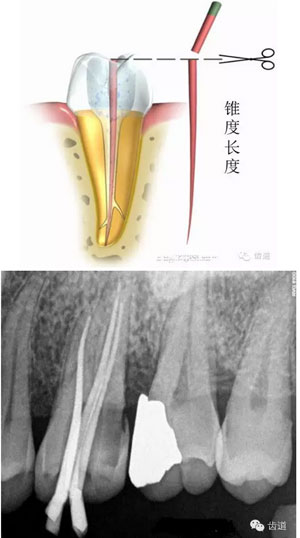

試尖,使其達(dá)到工作長(zhǎng)度,修整超出根尖孔的多余牙膠尖。選擇合適的牙膠主尖,距根尖0.5-1mm處卡住即可;或者選擇預(yù)備時(shí)最后一支銼相同型號(hào)的牙膠尖,尖端需剪去0.5mm。

根據(jù)根管大小選擇匹配攜熱加壓頭,攜熱加壓頭尖部據(jù)根尖5mm左右即可,用橡膠定位圈定位。同理,選擇合適的垂直加壓器